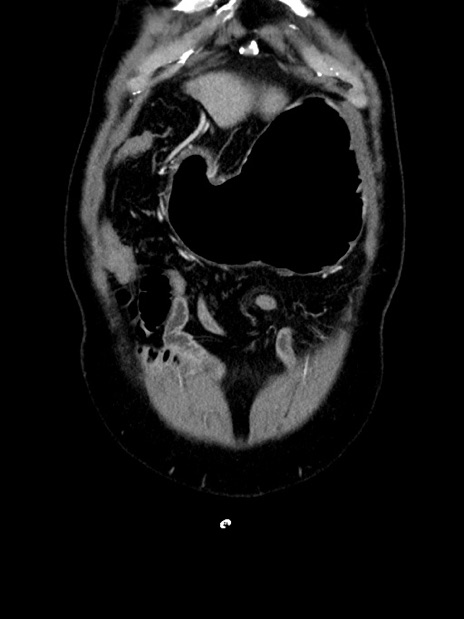

症例35(冠状断像)

横断像